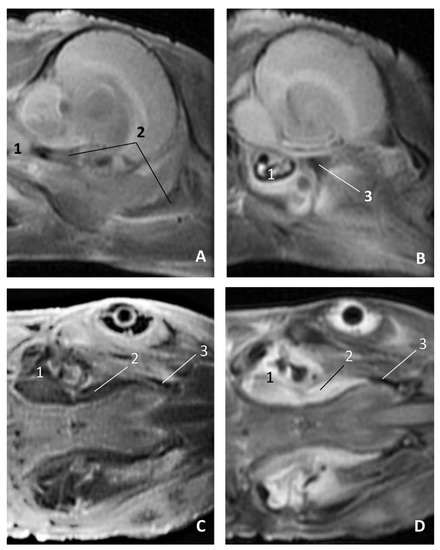

The MRI sagittal images show a pharyngeal cavity in a Globicephala melas fetus (gma1) and we could appreciate the oropharynx (fauces), the nasopharynx and the oesophageal vestibule hypointense in both T1 and T2 sequences(Figure 25A,B). Coronal T1 and T2 sequences show the piriform recess alongside the larynx (Figure 25C,D).

In MRI, we can appreciate, in early fetal stages, a bilateral structure within the laryngopharyngeal cavity, each named as a pharyngeal diverticulum of the auditory tube (PDAT). These are connected through the musculotubaric channel with the middle ear (temporal bone: petrous and tympanic part). In a young Delphinus delphis fetus (dde3), it appears in sagittal sections as a hyper/hypointense area seen caudal and rostrally, respectively (Figure 26A,B), and also in coronal sections (Figure 26C,D).

In older Delphinus delphis fetuses (dde5, dde8, dde11) this double space at both sides of the laryngopharynx is more evident and shows the same intensity, but now we can distinguish the vascular area (hyperintense) and the air-filled area (hypointense) (Figure 27, Figure 28, Figure 29, Figure 30 and Figure 31).

In more advanced fetal development, it is possible to observe air (hypointense) and vascular (moderate hyperintense) areas, and even the auditory tube (slightly hypointense) (Figure 30).

PDAT were clearly seen in sagittal and coronal sections in a Grampus griseus fetus (grgr1). The T2 sequences are clearer than T1 because they differentiate two areas: slightly hypointense (vascular) and hyperintense (air) (Figure 31).

Figure 25. Images of the oral and pharyngeal cavity. MR sagittal and coronal images are oriented so that the rostral is to the right. (A) T1 SE sagittal, (B) T2 FrFSE sagittal, (C) T1 SE coronal and (D) T2 FrFSE coronal planes. 5 months, gma1. 1, Hard palate; 2, Tongue; 3, Oral cavity (closed); 4, Oropharynx: fauces; 5, Oropharynx: soft palate; 6, Laryngopharynx: left piriform recess; 7, Laryngopharynx: oesophageal vestibule; 8, Epiglottis cartilage; 9, Epiglottic vallecula; 10, Arytenoid cartilages; 11, Nasopharynx; 12, Larynx.

Figure 26. Images of the pharyngeal cavity. MR sagittal and coronal images are oriented so that the rostral is to the right. (A) T1 SE sagittal, (B) T2 FrFSE sagittal, (C) T1 SE coronal and (D) T2 FrFSE coronal planes. 4 months, dde3. 1, Inner and middle ear; 2, Pharyngeal diverticulum of the auditory tube.

Figure 27. Images of the pharyngeal cavity. MR coronal and sagittal images are oriented so that the rostral is to the right. (A,B) T2 FrFSE sagittal, (C) T1 SE and (D) T2 FrFSE coronal planes. 5.5 months, dde5. 1, Inner ear; 2, Pharyngeal diverticulum of the auditory tube: moderate hyperintense area (vascular); 3, Pharyngeal diverticulum of the auditory tube: hypointense area (air).